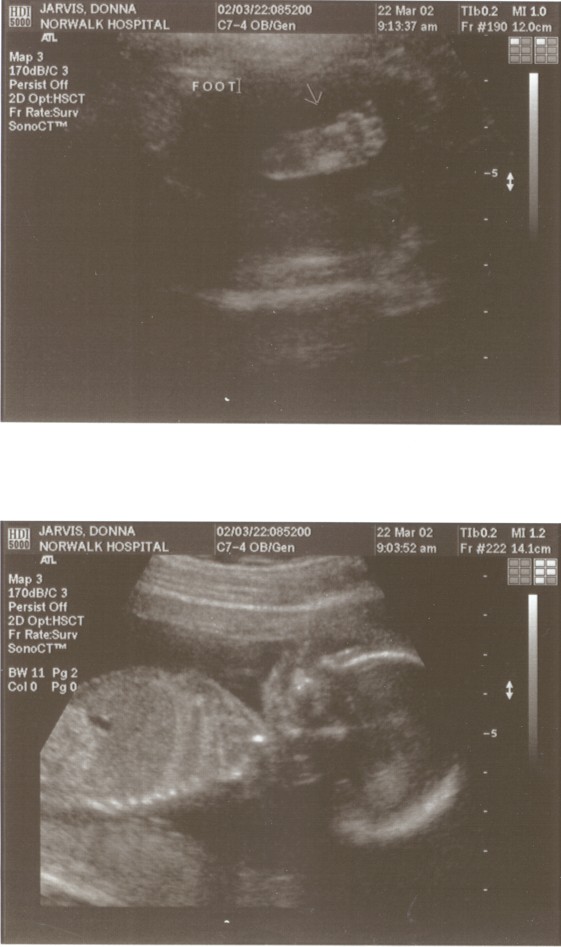

6/15/02 (Week 32)- We had our last ultrasound this week. The baby appears in good health and is estimated at 3 pounds, 14 ounces which is around the median size. We saw her lips and her tongue and watched her yawn. We also saw her little heart beating and watched her kick. Mom, however, is getting more and more uncomfortable - back aches, feet hurt, hands, feet and legs swollen. And she gained a little too much weight this visit, so we are now watching what we eat. We picked out our baby announcements this week and the room will finally be painted next week, so we are making some progress on getting everything done before the baby arrives!